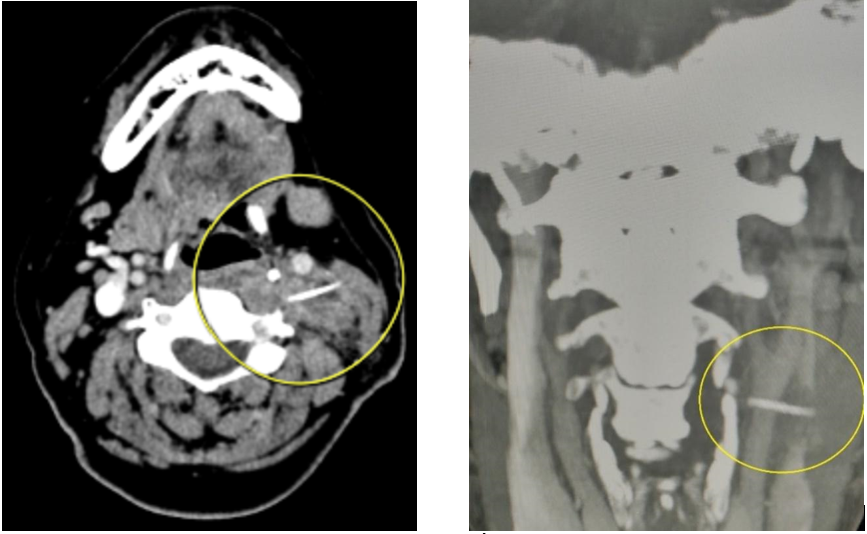

Bệnh nhân đã được khám lâm sàng kỹ lưỡng, nội soi tai mũi họng và chụp X-quang nhưng vẫn không phát hiện ra được dị vật. Các bác sĩ Khoa Tai Mũi Họng đã chỉ định chụp phim cắt lớp vi tính tiêm thuốc cản quang có dựng hình xương để đánh giá tình trạng ổ áp xe và xác định có dị vật xương cá ở vùng tổn thương hay không. Trên phim chụp cắt lớp, các bác sĩ đã phát hiện có dị vật xương cá ở vùng cổ dài khoảng 3 cm ở vùng cổ trái bệnh nhân. Điều đặc biệt, xương cá đã xuyên qua thành họng bệnh nhân nằm hoàn toàn ở phần mềm vùng cổ bên trái, và nằm ngay sau chỗ chia đôi của động mạch cảnh chung là một vị trí rất nguy hiểm có thể ảnh hưởng đến tính mạng.

Hình ảnh chụp cắt lớp vi tính